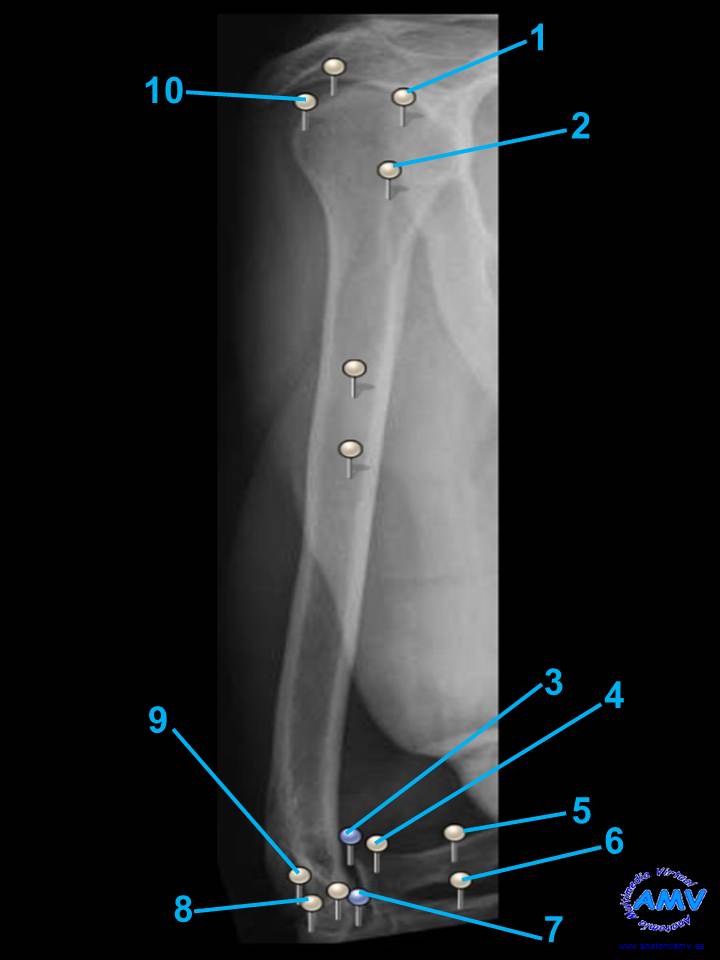

Radiografía del Brazo II

rx_ms_06.jpgIndique que estructura se señala con el número correspondiente:

El nº 1 señala .

El nº 2 señala .

El nº 3 señala .

El nº 4 señala .

El nº 5 señala .

El nº 6 señala .

El nº 7 señala .

El nº 8 señala .

El nº 9 señala .

El nº 10 señala .